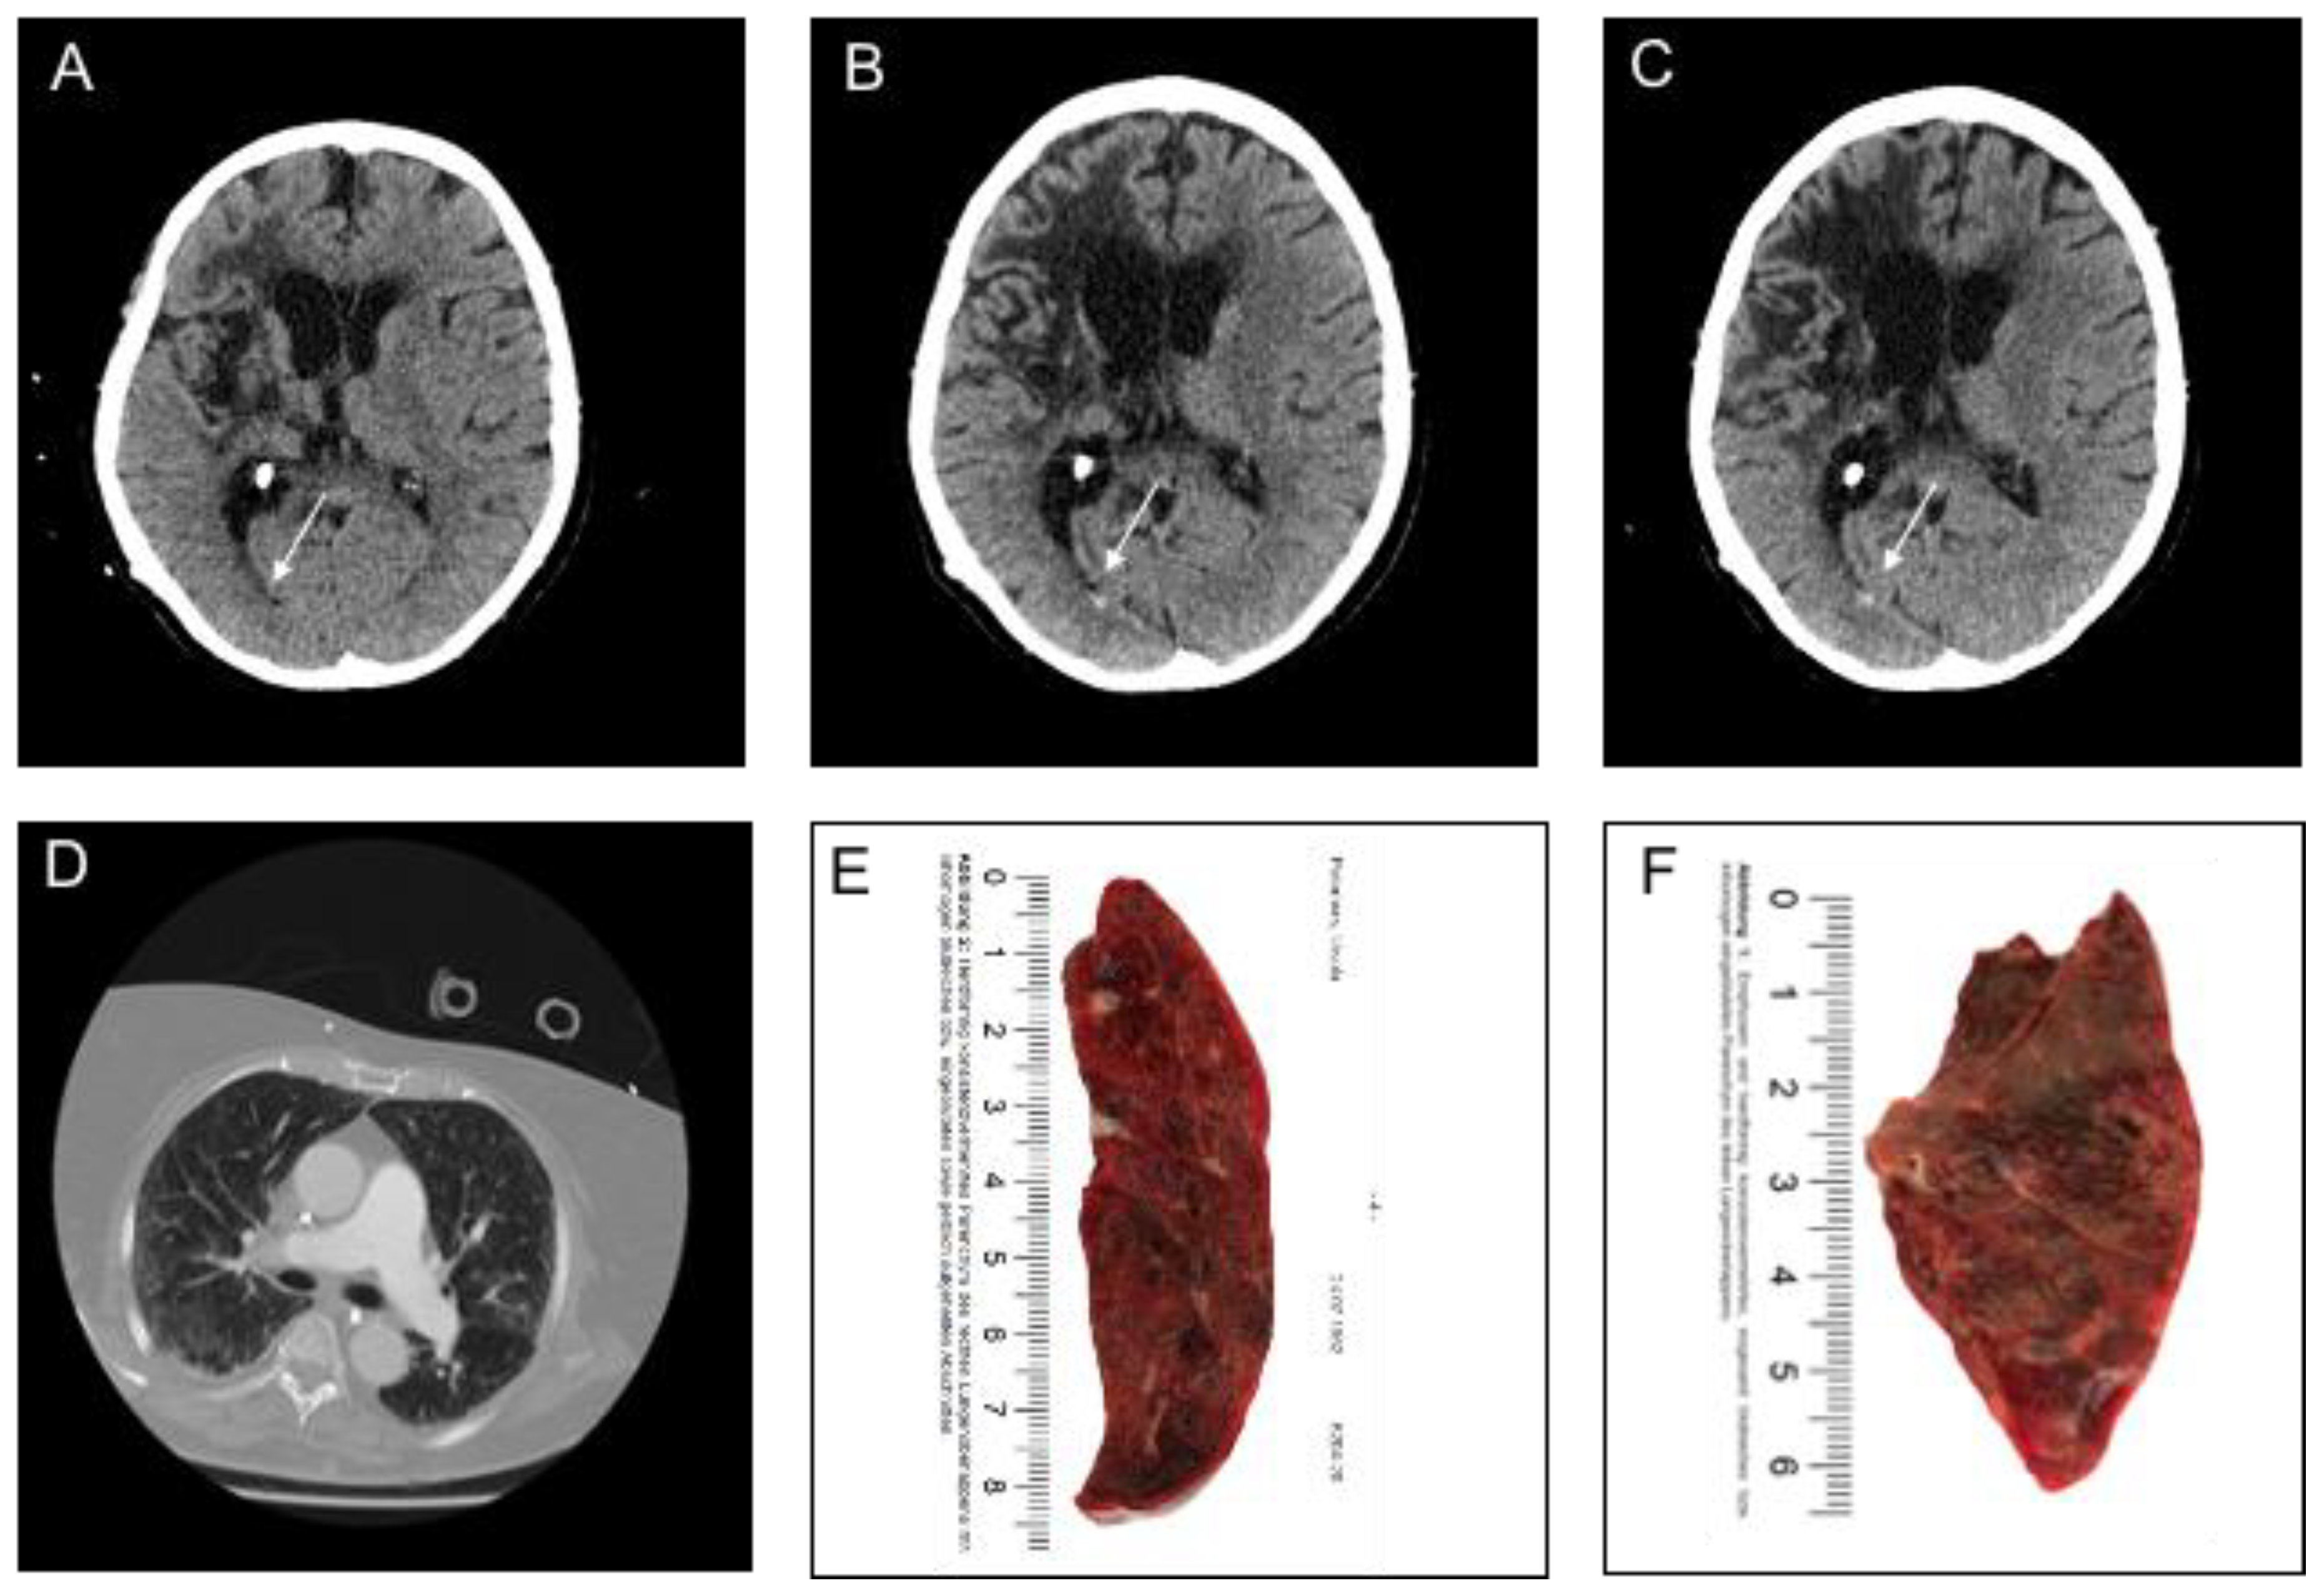

3.2. Imaging and Clinical Findings